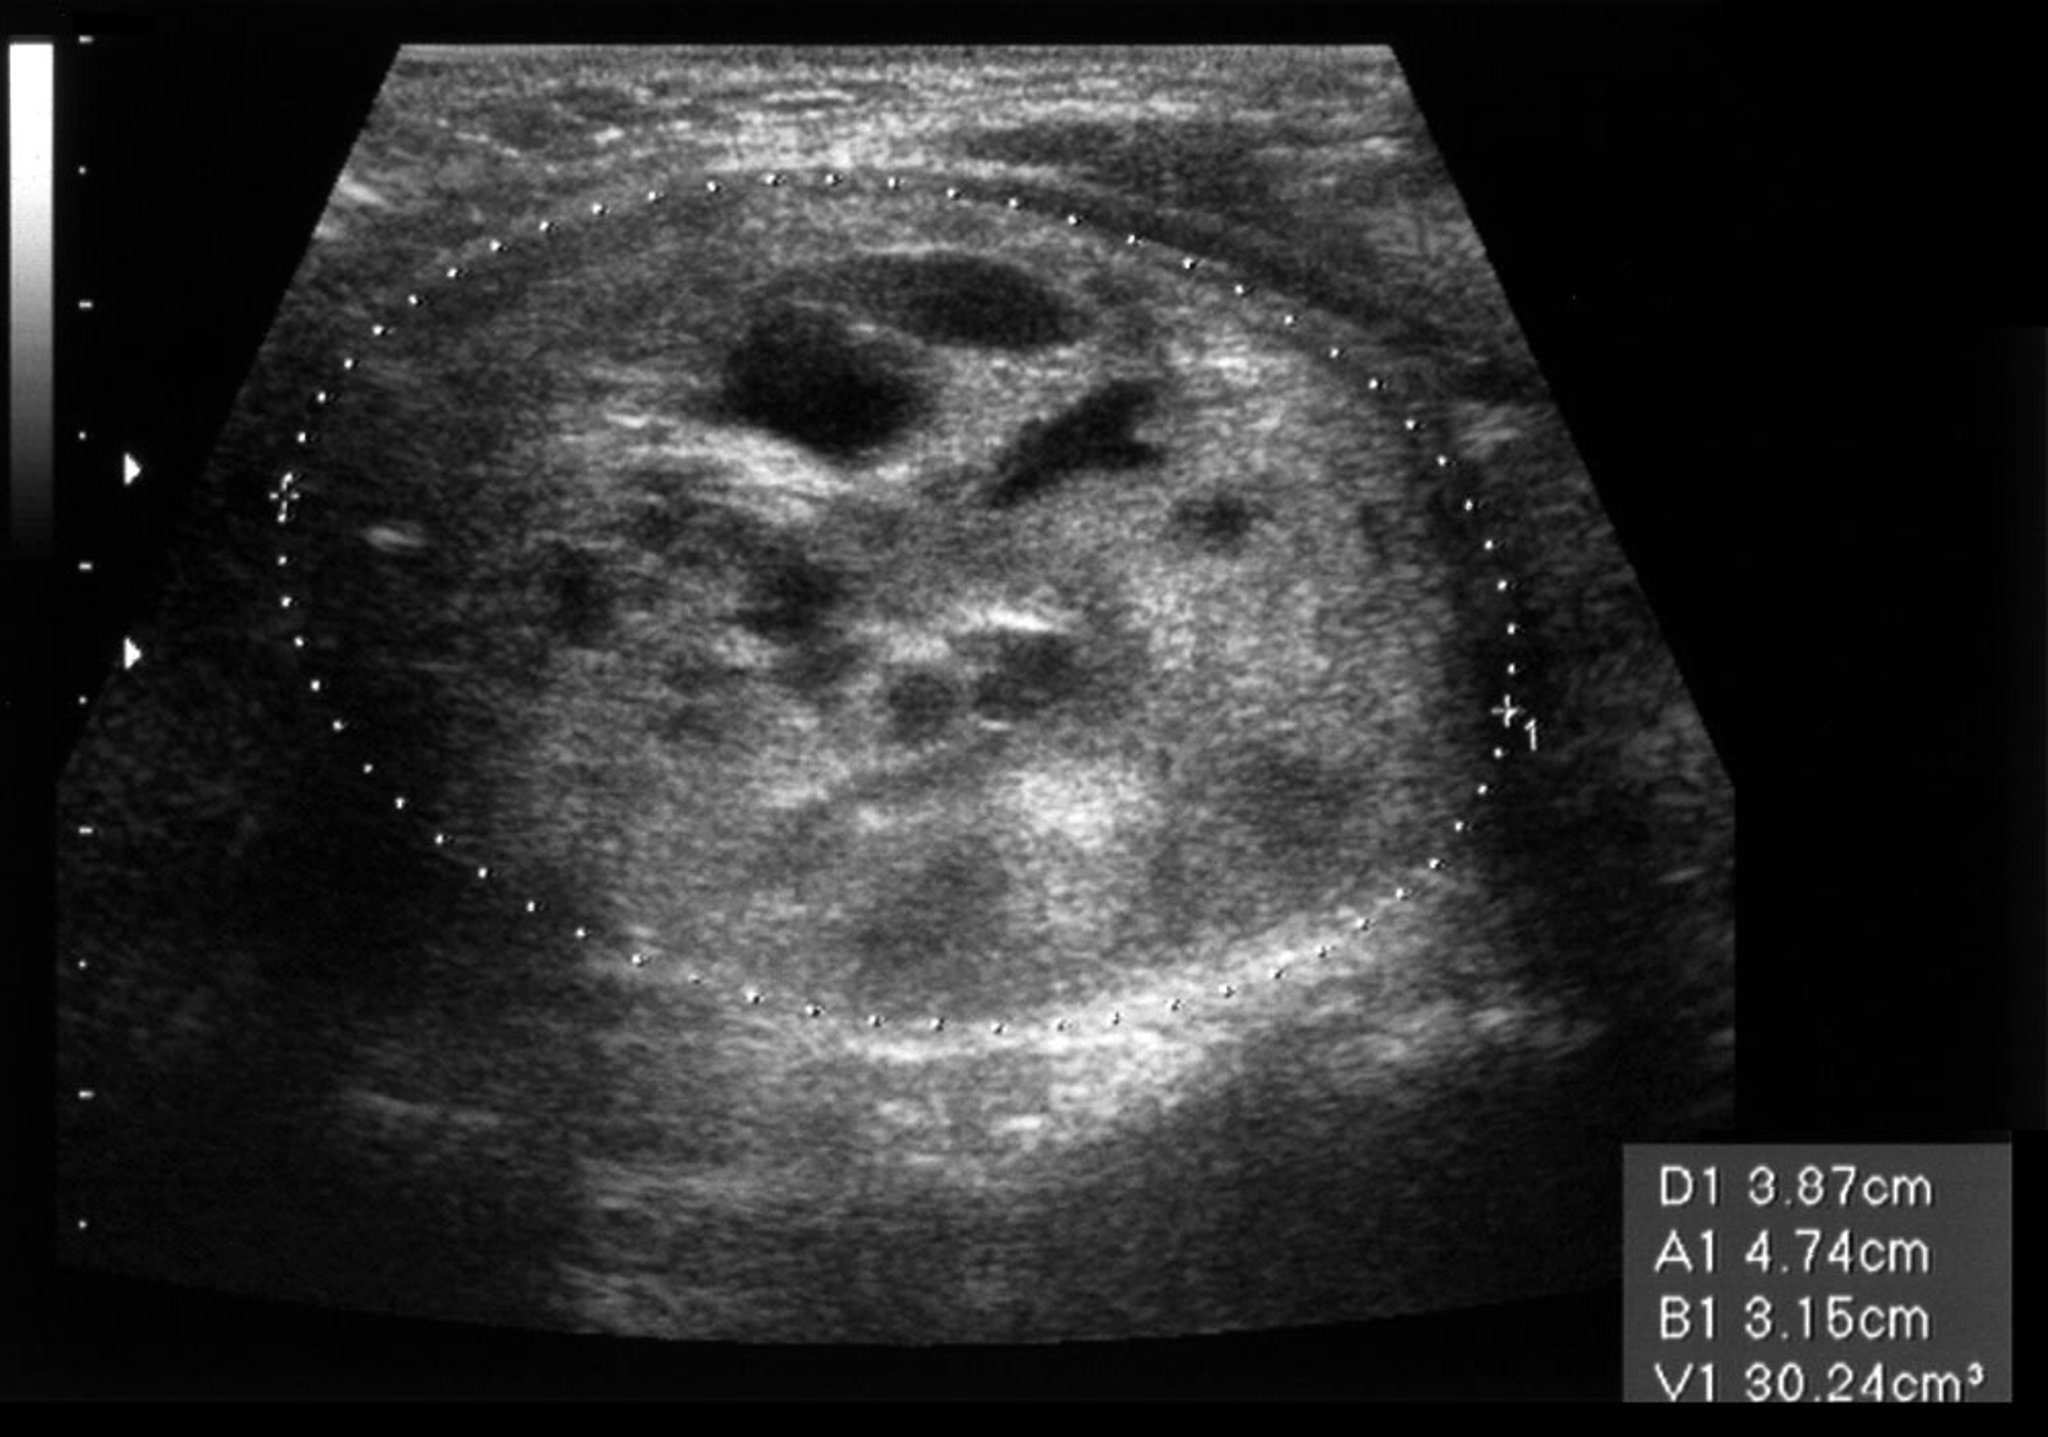

Thyroid Nodule (Ultrasound Scan)

This ultrasound scan shows a nodule in the left thyroid lobe. The nodule is 51 millimeters across on the longitudinal axis and 31 millimeters on the anteroposterior axis.